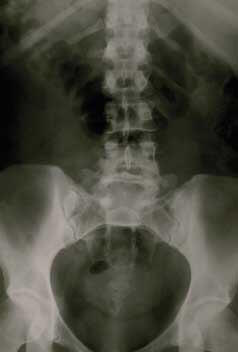

Les indiens maya, de leur côté, ne connaissent pas d'ostéoporose. Leur alimentation est constituée d'une quantité importante de plantes riches en phytoestrogènes. Ceux-ci protègent contre la diminution de la masse osseuse. De leur côté, les lignanes contenus en forte quantité dans différentes plantes assurent, par eux-mêmes, une différenciation métabolique des œstrogènes.

Au niveau du système osseux, un apport œstrogénique naturel sera bénéfique au même titre que de la vitamine D ou K, du calcium ou de l'exercice physique modéré.

Tout dépendra du tissu auquel elle va s'adresser. Pour le tissu osseux par exemple, l'activité œstrogénique maintient la densité osseuse et les cellules immunitaires. Elle accroît les possibilités pour les cellules tueuses de détruire les cellules cancéreuses.